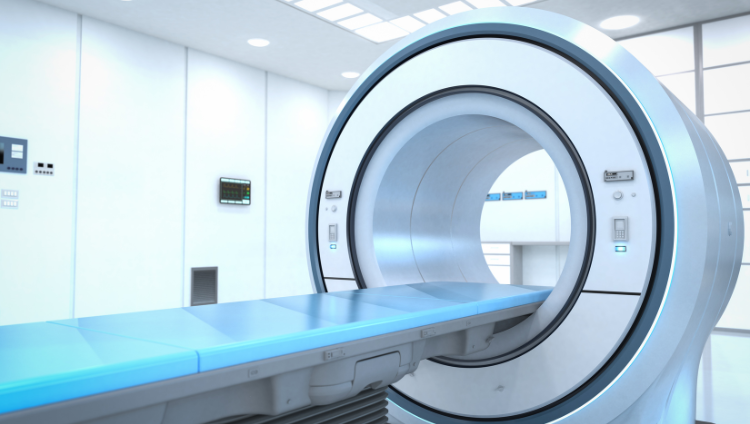

Advanced CT Scan Services

At Shiv Medicity, we offer high-precision CT scan services using the latest imaging technology to provide quick and accurate diagnoses for a wide range of medical conditions.